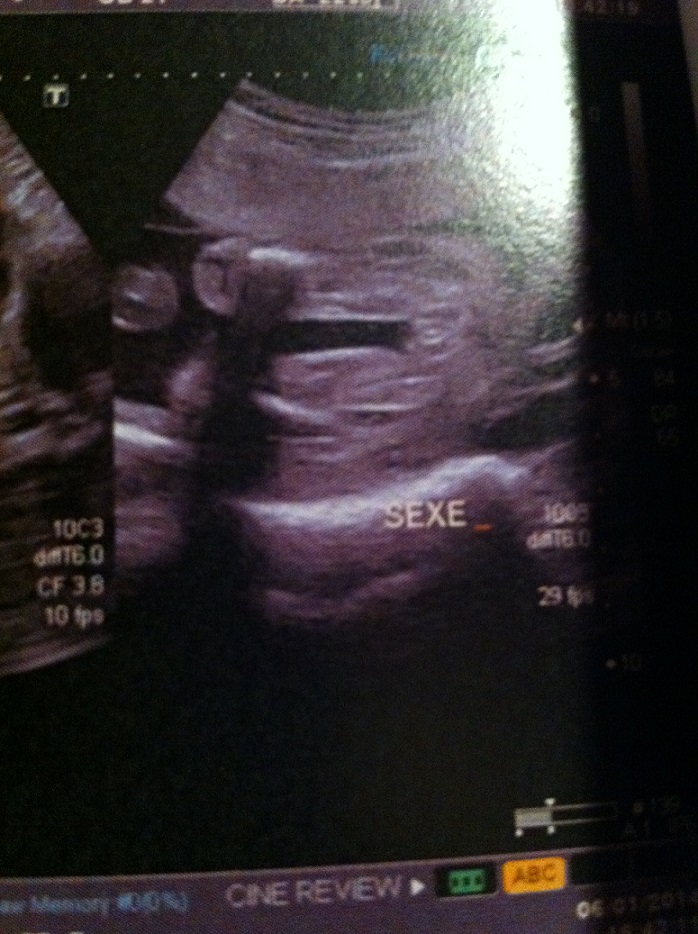

Browse Deactivated BSA Rifles for sale from our community of shooting enthusiasts on the UK's #1 gun marketplace Search, buy and sell Rifles on GunStar today!See what bebe sasa (bebesasa) has discovered on , the world's biggest collection of ideasBebe 22sa L'annonce du sexe du bébé se fait lors de la seconde échographie, entre la e et la 22e semaine de grossesse Mais tout dépend de la façon dont les organes génitaux se développent et du bon vouloir de bébé qui accepte, ou non, ce jourlà de dévoiler son sexe Découvrez les étapes mois par mois du développement du foetus au cours de la grossesse Abonnezvous à la chaîne

22 Sa Sexe Bebe Nouvelle Photo Echographie Connaitre Le Sexe De Votre Bebe Forum Grossesse Amp Bebe Doctissimo

Erreur Sur Le Sexe A 22sa Echographie Connaitre Le Sexe De Votre Bebe Forum Grossesse Amp Bebe Doctissimo

Vos Avis Echo 22sa 3 Echographie Connaitre Le Sexe De Votre Bebe Forum Grossesse Amp Bebe Doctissimo

Echo 22sa Fille Ou Garcon Echographie Connaitre Le Sexe De Votre Bebe Forum Grossesse Amp Bebe Doctissimo

Sexe A 22sa